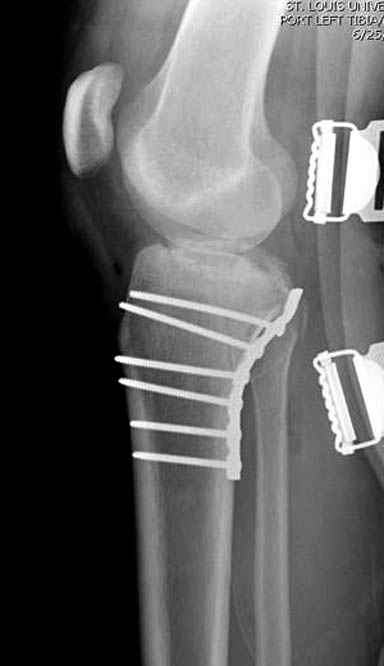

[Ortho] перелом мыщелка и диафиза большеберцовой кости - тактика?

Надеюсь, представленные снимки разных случаев помогут разобраться в тактике, и критика примется без личной обиды.

Имя     : 12 Med plateau fx.JPG

Тип     : image/jpeg